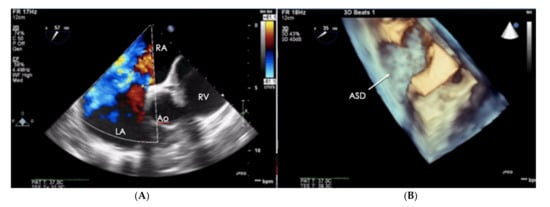

Figure 6.

Patient with PAH-CHD–atrial septal defect. (A) 2D-TTE visualization, short-axis view (SAX). (B) The same defect visualized in the transthoracic echo (TTE), 3D visualization. PAH-CHD: pulmonary arterial hypertension-congenital heart disease; 2D-TTE: two-dimensional transthoracic echocardiography.

When assessing the right heart′s size, the dimensions of the right atrium (RA) should not be overlooked (Figure 6). The linear dimension of RA should be marked in the 4CH view, perpendicular to the long axis of the heart (Figure 7) [23]. However, more valuable in terms of clinical significance is the RA volume, also measured in the 4CH view [23]—an RA area greater than 18 cm2 indicates enlargement and is one of the most common echo abnormalities found in PAH patients [24].